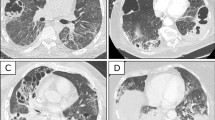

In COVID-19, the lower left and lower right lobes are most commonly afflicted according to radiographic abnormalities5,24, and these are typically the gravitationally dependent regions of the lung in either upright or supine positioning. However, even with an extreme baseline perfusion gradient of 100% (corresponding to 0-1/3-2/3 distribution), Fshu:Finj in the model is still limited to 2 at most. For example, in Fig. 3, Fshu:Finj does not exceed 3 even at 100% baseline perfusion gradient until the resistance reduction is 40% for Finj = 10%, or 55% for Finj = 20%. Therefore it appears unlikely that the degree of pulmonary shunt reported in COVID-19 patients (Fshu = 50% and Fshu:Finj = 3) could occur without a substantial degree of vasodilation and hyperperfusion in the small fraction of injured lung, if one also assumes there is negligible venous admixture from other mechanisms producing ventilation-perfusion mismatching.

Massive pulmonary embolism is often accompanied by dyspnea and chest pain28, but is also commonly silent29. With mild or moderate pulmonary embolism, ventilation-perfusion mismatching in noninjured regions and/or vasodilation in injured regions remain necessary to explain Fshu:Finj ≥ 3. A case report using dual-energy CT demonstrated no obvious indications of pulmonary emboli in the well-aerated lung, but rather vasodilation of pulmonary arteries and hyperperfusion adjacent to infected regions, concluding that a likely explanation for hypoxemia involves “intrapulmonary shunting towards areas where gas exchange is impaired”10. Another case report found pulmonary embolism as well as vasodilation in the regions of ground glass opacification21. Vascular enlargement has been a common radiographical finding22. A recent study highlighted the prevalence of perfusion defects affecting large lung fractions in mechanically ventilated patients with severe COVID-19, as well as dilation of peripheral vessels30. Thus, there is strong clinical evidence of vascular dysregulation in the lungs, and there may be potential for poorly aerated injured regions to exhibit at least impairment of HPV if not vasodilation.